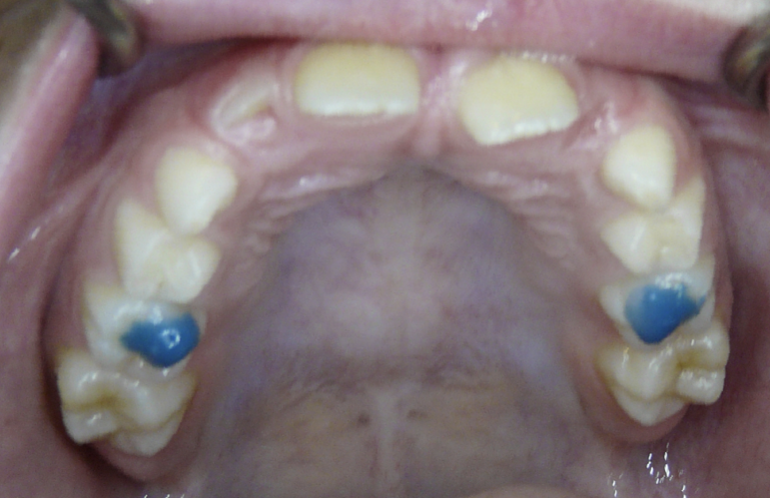

Ectopic Eruption

Ectopically erupting maxillary molar